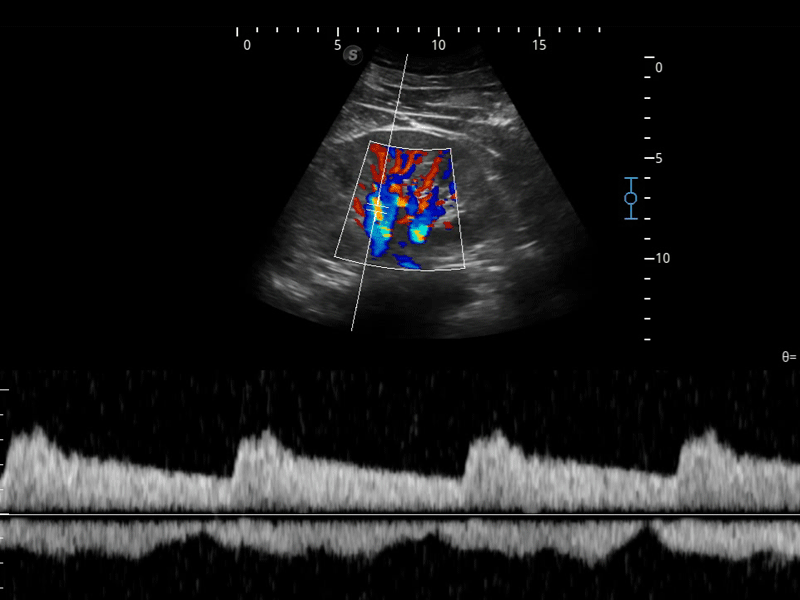

组织多普勒

组织多普勒成像功能,可提供心肌运动速度和其他临床信息,使临床医生能够分析和比较患者心脏不同部位的运动。

临床图像